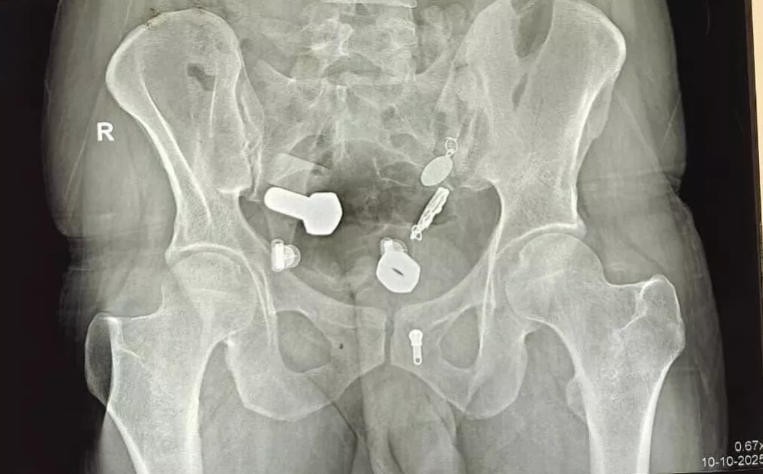

按常规流程,医生给他开了影像学检查,结果拍完片子,大家都惊呆了。

他的消化道简直能开家五金店:螺母、螺栓、金属棒、铁钉、别针……什么都有,而且它们都已经随肠胃运动来到了大肠里,估计已经吞下很久了。

(医学影像)